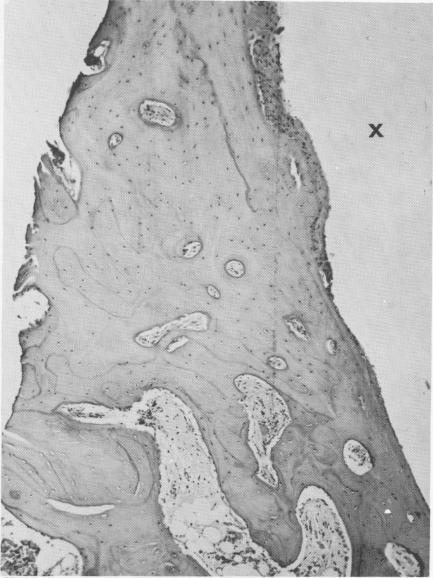

Fig. 4-63. A longitudinal section shows dense bone with numerous osteocytes around the implant site (X). (From Linkow, L. I.: Alloplastic implants. In Goldman, H. M., Forrest, S. P., Byrd, D. C., and McDonald, R. E.: Current therapy in dentistry, ed. 3, St. Louis, 1968, The C. V. Mosby Co.)

Fig. 4-62. The dense fibrous tissues around the implant site (X) is tightly bound to healthy bone, as seen in cross section. (From Linkow, L. I.: Alloplastic implants. In Gold-man, H. M., Forrest, S. P., Byrd, D. C., and McDonald, R. E.: Current therapy in dentistry, ed. 3, St. Louis, 1968, The C. V. Mosby Co.)

3 Dense bone with numerous osteocytes around vent plant implant site

2 Dense fibrous tissues at vent plant implant site bound to healthy bone